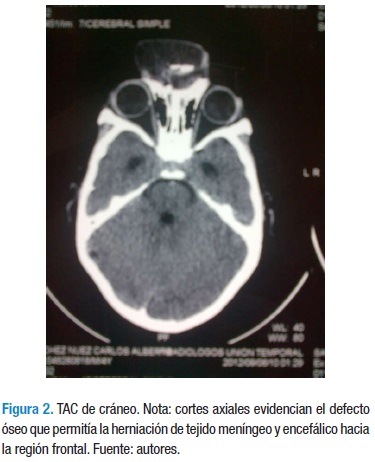

Encefalocele Frontonasal Reporte De Un Caso Con Diagnostico Prenatal